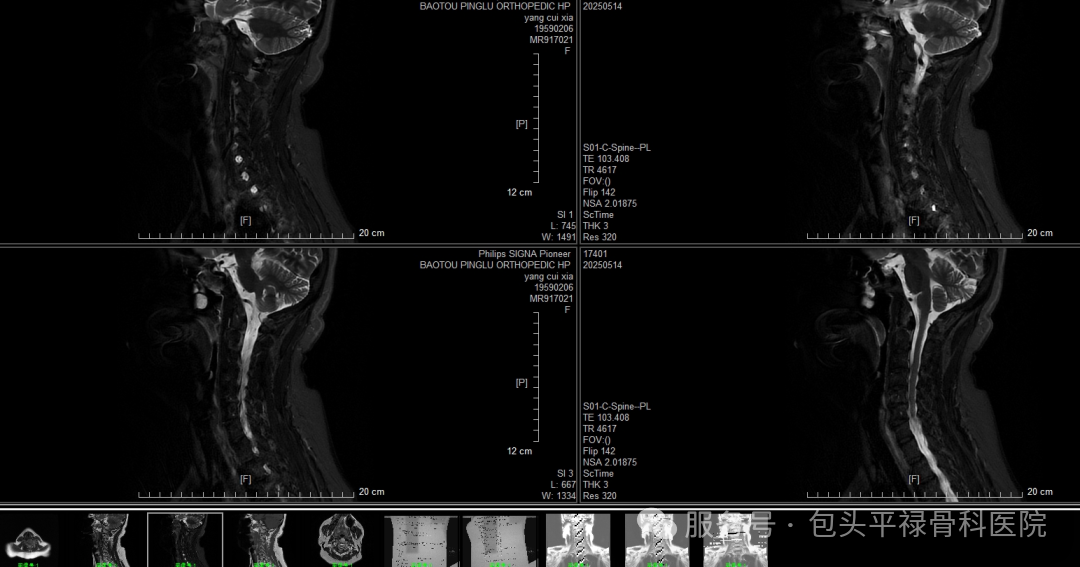

DR-CT-MRI影像对比

图源:包头平禄骨科医院

MRI,即磁共振成像,其工作原理是通过磁共振设备,让人体中的氢原子产生共振,再平静下来,根据振动和平静之间的能量差进行成像,观察正常组织与患病部位之间的能量信号差异。对于软组织、肌肉组织、神经组织的探索能力较强。

适用于全身部位及多种疾病的检查、诊断,对脊柱、关节、肿瘤、淋巴结和血管结构的相互识别具有独特优势。骨科方面,对于椎间盘突出、肩袖损伤、膝关节韧带及半月板损伤等疾病的检查,医生们更倾向于优先选择MRI。

优点:软组织显示清晰,能多维度提供病灶信息;没有骨性伪影,无辐射

缺点:费用高、检查时间较长、不适用于体内留有金属物品者